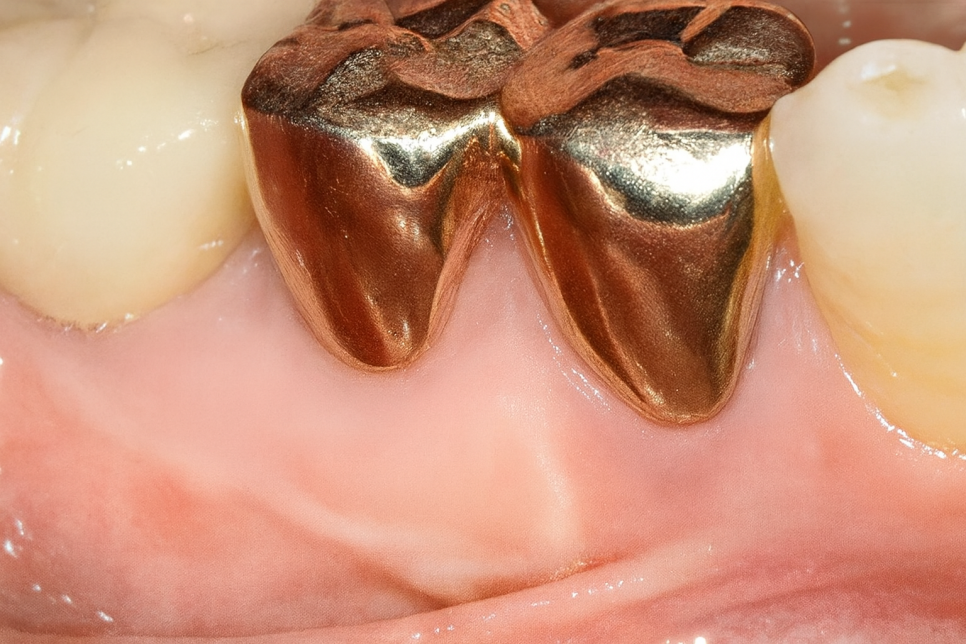

Q. 얼마나 있어야 충분한 걸까요?

The width of the attached gingiva — Much ado about nothing? / journal of dentistry 38 (2010)

관련된 한 논문을 선유도역 치과 에서 준비해 봤습니다.

여러 논문을 리뷰해서 정리한 건데,

이 가운데 한 논문에서는 2mm 이상이

필요하다는 연구도 있었습니다.

또한 이 외 다른 논문에서 몇몇 저자는

1mm 이하가 되어도 충분하다 말하는 반면

다른 이들은 각화 조직의 높이가

3mm는 넘어야 된다 말하고 있습니다.

더불어 높이뿐만 아니라 분포가 균일하게

어느 정도 확보되어야 된다 하는 이들도 있었죠.

만약 이보다 적다면 근단변위판막술이라는

수술을 통해 어느 정도 양을 확보해 주어야 됩니다.

Q. 근단변위판막술은 뭔가요?

이 수술은 잇몸의 위치를 바꿔

유동성이 있던 부분을 뼈와 붙어 단단하게

만들어주는 과정입니다.

움직임이 있는 부분을 아래로 끌어와

단단하게 각화 되도록 유도함으로써

방패 역할을 해줄 부위를

충분히 확보하는 과정을 말하죠.

까다로운 과정이 요구되기 때문에

의료진의 경험과 실력이 중요한 수술이죠.